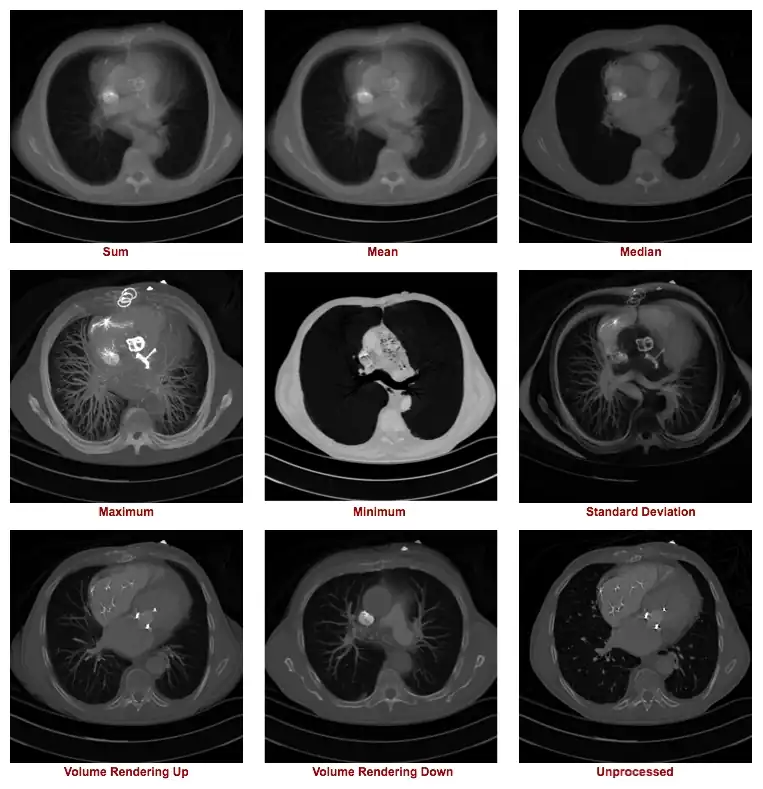

The figure below illustrates the outcome of a range of z-projection methods, with a single slice shown in the bottom right hand corner for reference purposes. The first image in the top left shows the result of summing 16 slices, and the other two images on that row show the results of computing the mean and median of these slices.

The first two images in the second row show the result of what are called a Maximum Intensity Projection (MIP) and a Minimum Intensity Projection (MinIP), respectively. A MIP evaluates each voxel along each line of voxels through the volume to determine the maximum voxel value and forms an image using the values so determined for each line. A MinIP uses the minimum voxel values, as illustrated in the following figure:

Notice that volume rendering can be applied from distal to proximal slices, as illustrated in our figure, as well as in the opposite direction, i.e. from proximal to distal slices. Hence the terms Volume Rendering Up and Volume Rendering Down used in our set of nine example images above.

The type of axial projection method appropriate to an individual patient study is dependent on the anatomical and/or functional information of relevance to the diagnostic process. Let's take the case of imaging contrast-filled blood vessels, for example, in our nine example images above. Note that a MIP can be used to give a visually-stunning impression of the vessel bed in the patient's lungs. There's little depth information in this projection, however, so that overlapping and underlying vessels can obscure lesions that might be present in blood vessels of interest. The application of this form of axial projection to angiography is therefore limited to studies where vessel overlap isn't an issue. The inclusion of voxel transparency and depth weighting in volume rendered images addresses this limitation of MIP processing.